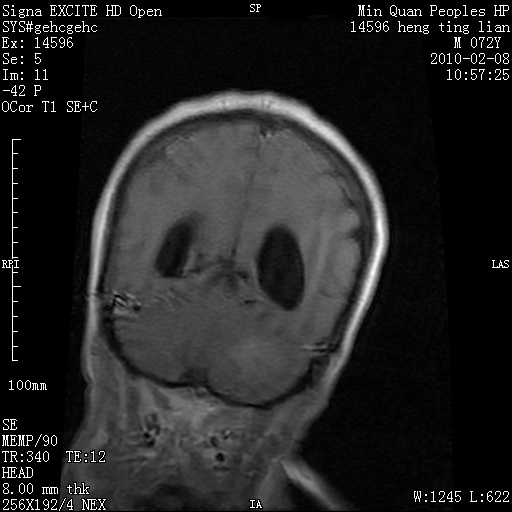

m,72,头疼,头晕两年,伴视力模糊三月,饮食呛咳两天。pe:颈部抵抗,左眼突出,左眼瞳孔约3mm,对光反射消失,双眼失明,伸舌困难,双肺呼吸音粗,心率110次/分,左上肢肌力i级,左下肢屈曲,肌张力高。现有08年2月19mri平扫及10年2月8日mri增强请会诊。ct病灶呈低密度伴散在点、片状等密度区,无明确钙化(无ct片资料可供上传)。[

脑外肿瘤,囊实性,环状不规则强化,内听道扩大,考虑神经源性肿瘤

左侧桥小脑区占位伴梗阻性脑积水----考虑 1神经鞘瘤 2室管膜瘤。

左侧桥小脑区神经鞘瘤伴梗阻性脑积水。

脑外肿瘤,病灶呈匍匐蔓延,表皮样囊肿可能性大。